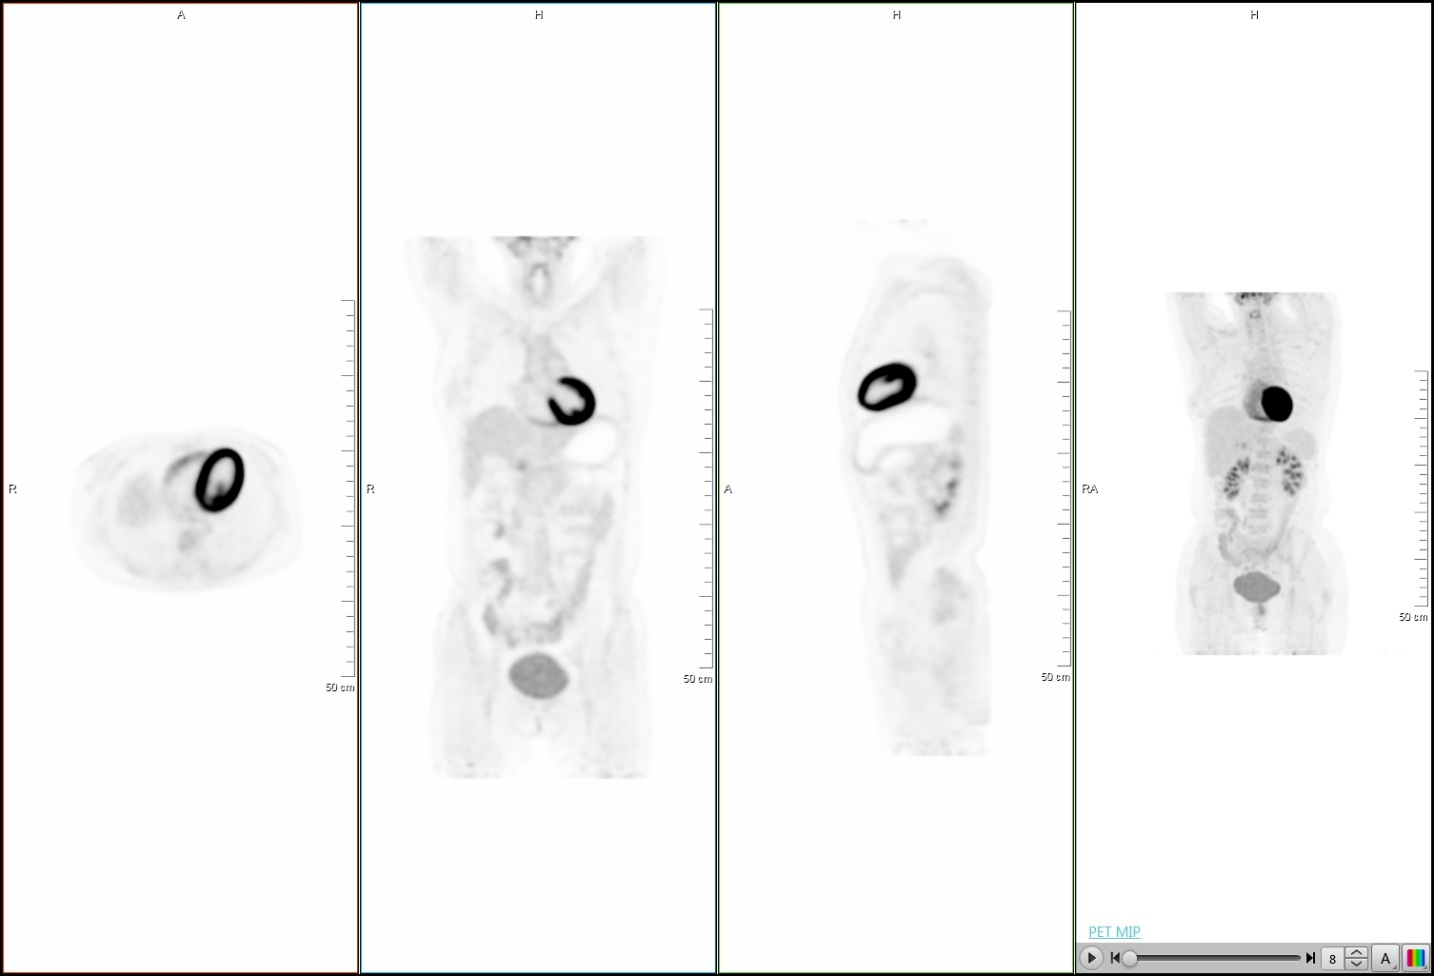

下面的临床图像展示了uMI 510光导PET-CT的优异性能:

超清PET图像

脑部图像

心脏成像

大体重病人低剂量

以下是中山医院两台PET-CT设备临床图像对比:

淋巴瘤治疗后随访病例

同一时间不同设备对比显示淋巴结

通过两台设备临床图像的对比分析可看出,联影PET-CT图像分辨率更高,对比度更优,能更好的满足临床科室的需求。